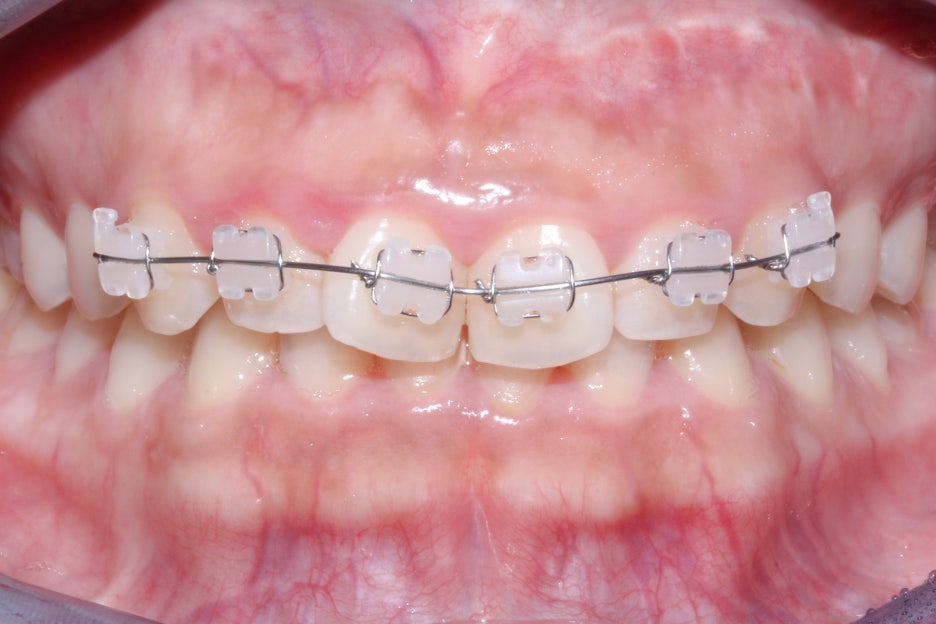

세라믹교정 초기에는 위처럼 본격적인

치아교정을 위한 브라켓을 부착하게 되는데요,

위의 Case는 상악 전치부만 부분교정을 진행하기 때문에

6개의 치아에만 브라켓을 부착한 상태입니다.

세라믹 교정장치는 위처럼 치아색상과 유사한

세라믹 소재의 브라켓을 사용하기 때문에

심미성이 높은 편인데요, 다만 가로로 지나가는

교정철사와 ligature wire가 노출되기 때문에

2D교정이나 투명교정과 같은 완벽한 심미성은

기대하기 어렵습니다.

유의미한 교정효과가 보장되기 때문에

여전히 많은 사랑을 받는 교정 장치입니다.